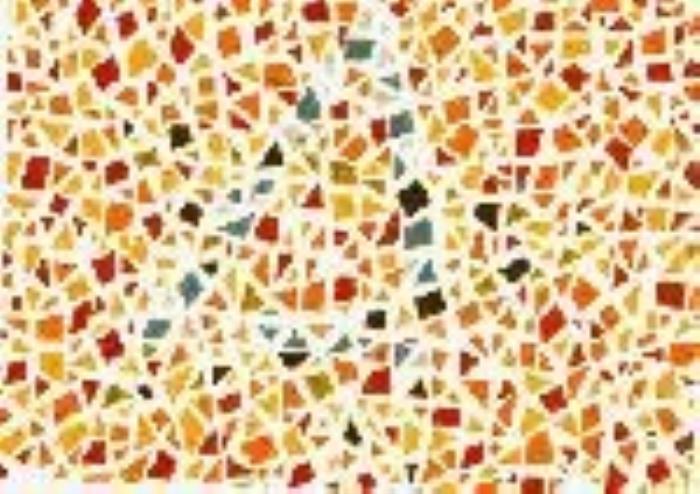

(正常 绿色盲 红色盲 蓝黄色盲)

(正常 绿色盲 红色盲 蓝黄色盲)

根据不同类型的色盲,以及色盲的严重程度,患者多少是能看到一些颜色的,或者说只是有些颜色看起来跟常人不同,但并不等于是“黑白”的世界。